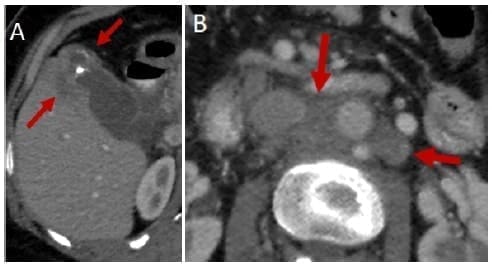

La ecografía abdominal debe hacer sospechar un CVB cuando hay engrosamiento focal e irregular de la pared de la vesícula o cuando el espesor es mayor de 10 mm. La TC y la RNM son más útiles para evaluar la extensión de la enfermedad o cuando hay masas vesiculares de buen tamaño 49 (Figuras 2 y 3).

Figura 3. Tomografía axial que muestra masa en el fondo de la vesícula (A)

y compromiso ganglionar para aórtico (B)